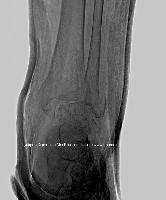

Магнитно-резонансная томография (МРТ):один из самых эффективных методов диагностики заболеваний